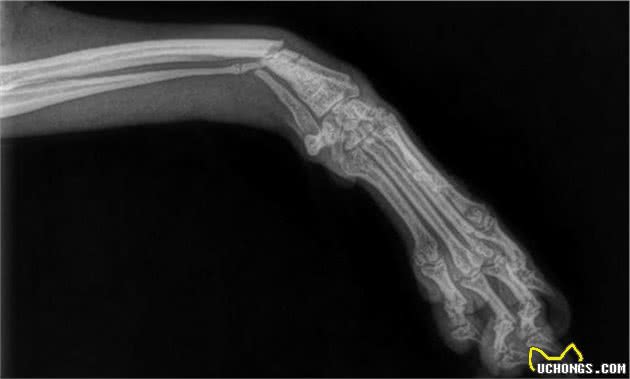

骨折后可能出现两种情况,一种是骨骼位置不变,另一种是骨骼发生移位,骨骼位置没有发生改变的,可以用石膏固定,等待骨骼自然愈合,骨骼的固定方法多种多样,可以根据情况加以选择。如果骨骼发生移位,就需要先矫正骨骼位置再加以固定。

因为骨骼周边的肌肉组织存有支撑力,纯粹纠正骨骼部位很有可能不可以长期维持,这个时候,和医治人们骨骼挪动的方式 一样,可以经过手术治疗,用钢钉、港口螺钉或是金属材料板材等固定不动骨能,可是,因为这一些全是金属制造,在其中容积较小的很有可能会因为承受力而弯曲,容积很大的也必然会在日后狗狗做运动过量的情况下弯曲、破裂。

给人固定不动骨骼的情况下只需确保骨骼在没有主题活动的情况下不挪动就可以了,而给狗狗固定不动骨骼的规范要高许多,要确保即使狗狗略微主题活动骨骼也不会挪动、不容易再断裂。

但是,骨骼比较脆弱,一旦固定住,就不能再接受外界作用力的刺激。一旦受到刺激,身体可能就会产生“不需要这段骨骼”的错觉,造成骨骼连接处的骨物质融化,变得像融化了的威化饼一样。另外,固定用的钉子、钢丝、螺丝和金属板等可能会阻碍骨骼周围的血液流通,延缓骨骼面生。因此,越想牢牢固定可能就越容易产生相反的效果,这是一个恶性循环,要是骨骼迟迟不愈合,固定用的金属制品又断裂了的话,可能就需要进行二次手术,但是,因为此时骨骼更加脆弱,上次手术留下的伤口也还在,手术的难度可能更大。